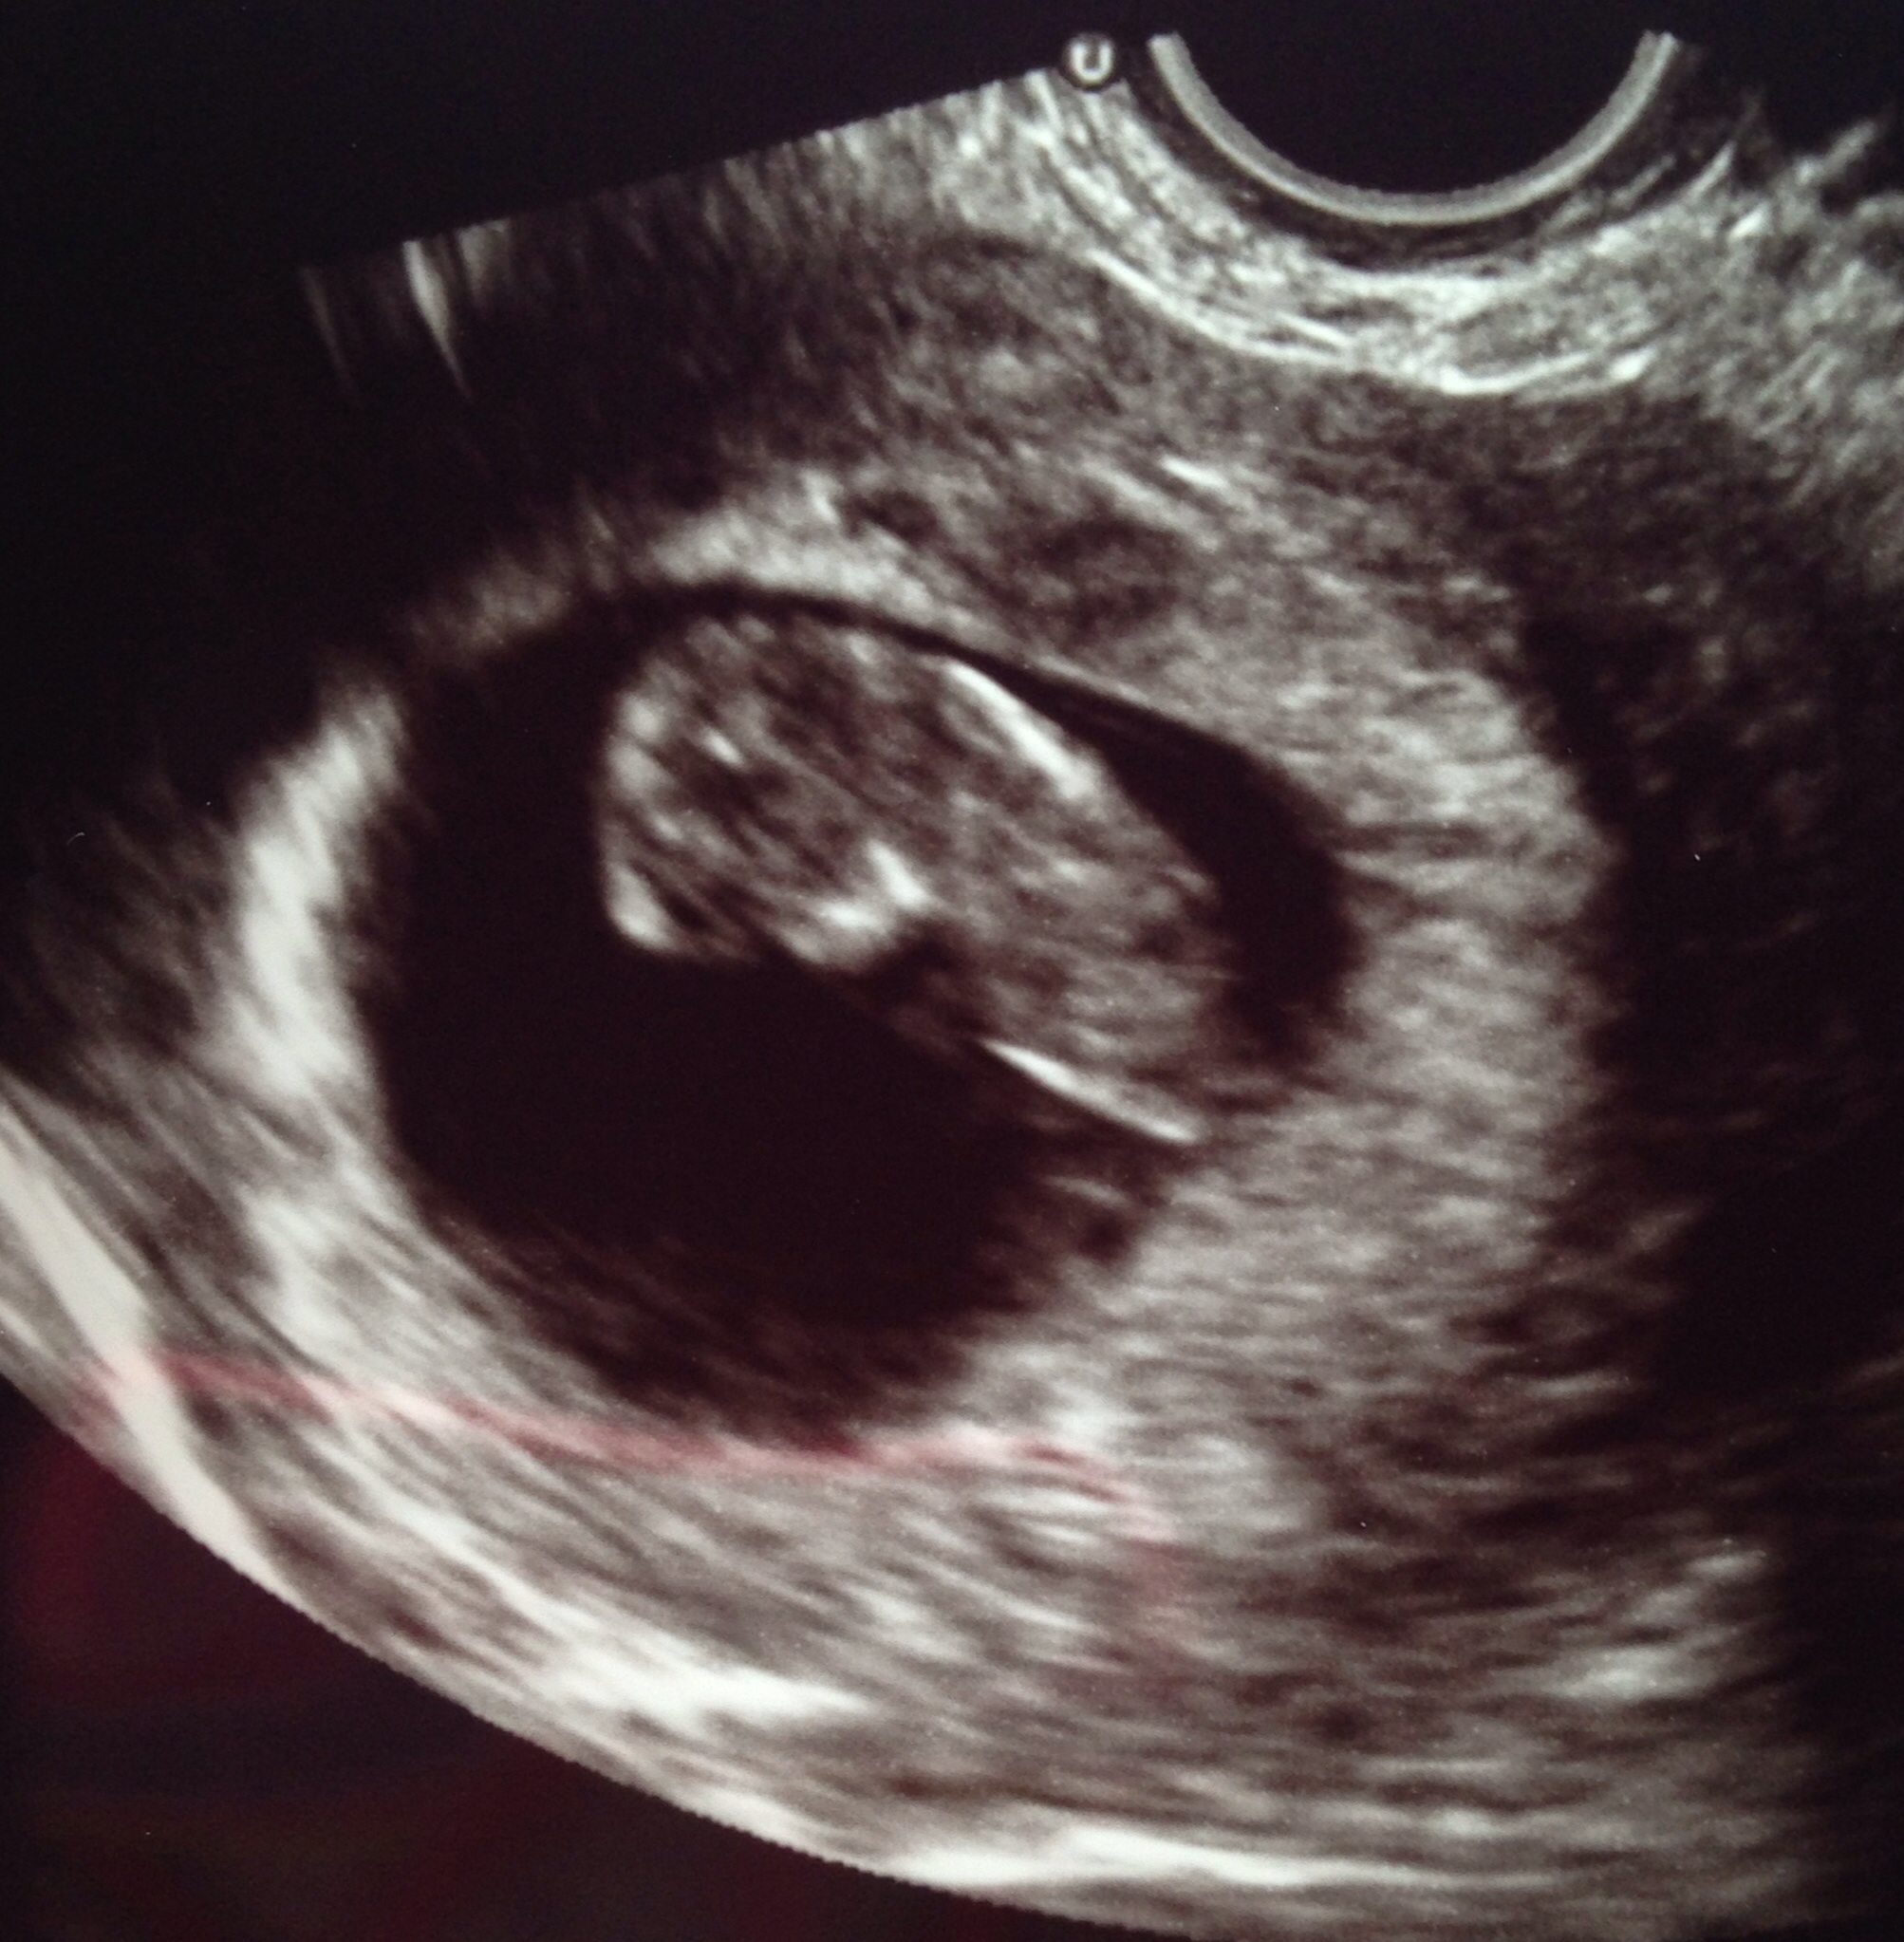

Went to check on baby this morning! Perfect heartbeat and baby was kicking and waving around like crazy! It's amazing that all of that can be happening and I feel nada. Here is our peanut!